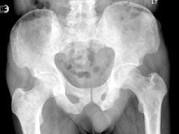

问题 男,77岁,全身性骨痛,夜间加重,贫血,PSA大于100,结合图像,最可能的诊断是?(?)

选项 A.成骨性骨转移 B.多发性骨髓瘤 C.慢性化脓性骨髓炎 D.骨肉瘤 E.以上都不是

答案 A